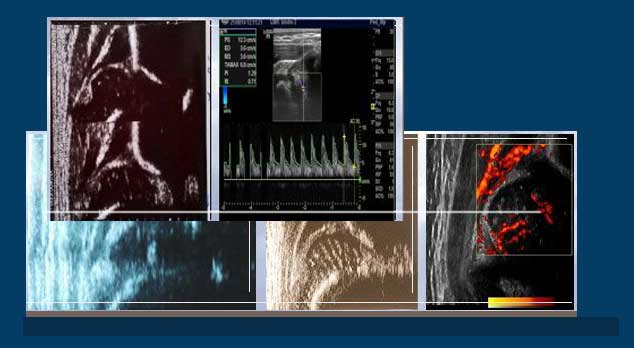

Marzenie ortopedów o wykryciu wady od urodzenia i zobaczeniu ukrwienia stawu biodrowego spełniło się, leczenie stało sie bezpieczniejsze ,ryzyko martwicy głowy kości udowej zmalało.Rozwój apartów usg pozwala zobaczyc coraz dokładniej nieprawidłową budowę nawet najmniejszych elementów biodra u noworodka .

3.Tylko lekarz z odpowiednią wiedzą i doświadczeniem potrafi na podstawie osobiście zrobionego badania ultrasonograficznego trafnie zdiagnozować wrodzone zwichniecie stawu biodrowego i zastosować odpowiednie leczenie.